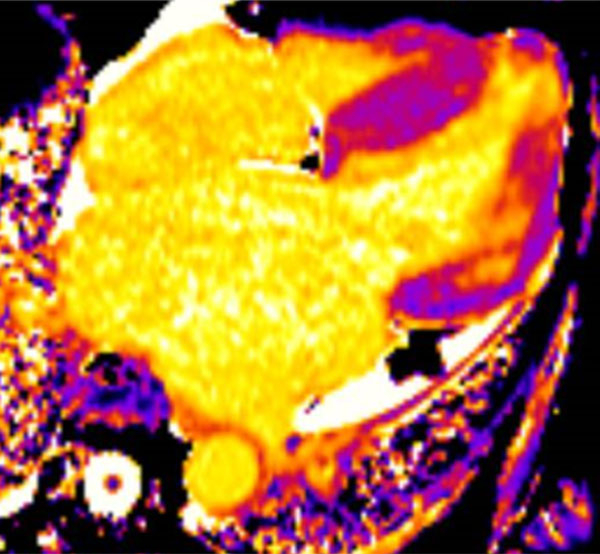

C : T1 mapping

Figure 6 : T1 natif légèrement augmenté dans le septum et la paroi latérale (fibrose)

Figure 7 : T1 post-contraste diminué à l’apex (nécrose)